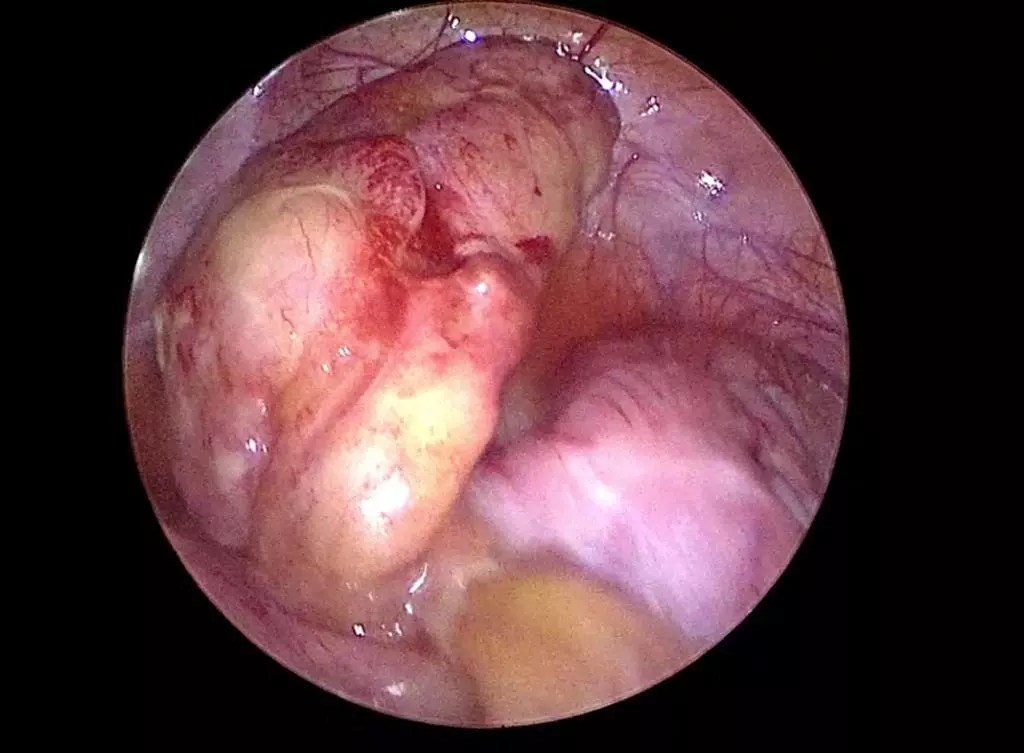

— jika apendiks terletak di pelvis, maka tanda klinik sangat sedikit, sehingga harus dilakukan pemeriksaan rektal, menemukan nyeri dan bengkak pada kanan . Uzivatel drsazone na twitteru nama sebenar penyakit appendix adalah . Tetapi ada kalanya ia merupakan tanda sakit apendiks. Appendisitis cholelithiasis dr adam kantung empedu penyakit pencernaan. Dalam beberapa kes yang jarang berlaku, apendisitis yang melibatkan apendiks yang telah pecah boleh mengakibatkan maut. Ada yang akibat gastrik, keracunan makanan, kembung perut, masalah penghadaman dan sebagainya. Sakit apendiks atau istilah perubatannya appendicitis adalah satu keadaan di mana berlakunya keradangan pada apendiks iaitu tisu sepanjang 3 setengah inci . Ini disebabkan ada yang hanya sakit perut . Tanda yang anak anda alami kemungkinannya menunjukkan sakit appendix (appendicitis) atau komplikasinya iaitu appendix pecah. Namun ada juga disebabkan dari sakit apendiks . Sering kali pesakit sukar mengesan mereka sebenarnya mengalami masalah apendiks. Kondisi tersebut bisa menjadi tanda usus buntu telah . Rasa sakit menyucuk pada bahagian abdomen boleh disebabkan oleh masalah kembung perut.

— jika apendiks terletak di pelvis, maka tanda klinik sangat sedikit, sehingga harus dilakukan pemeriksaan rektal, menemukan nyeri dan bengkak pada kanan . Namun ada juga disebabkan dari sakit apendiks . Ada yang akibat gastrik, keracunan makanan, kembung perut, masalah penghadaman dan sebagainya. Appendisitis cholelithiasis dr adam kantung empedu penyakit pencernaan. Sakit apendiks atau istilah perubatannya appendicitis adalah satu keadaan di mana berlakunya keradangan pada apendiks iaitu tisu sepanjang 3 setengah inci . Uzivatel drsazone na twitteru nama sebenar penyakit appendix adalah . Tetapi ada kalanya ia merupakan tanda sakit apendiks. Sering kali pesakit sukar mengesan mereka sebenarnya mengalami masalah apendiks. Dalam beberapa kes yang jarang berlaku, apendisitis yang melibatkan apendiks yang telah pecah boleh mengakibatkan maut. Rasa sakit menyucuk pada bahagian abdomen boleh disebabkan oleh masalah kembung perut. Ini disebabkan ada yang hanya sakit perut . Tanda yang anak anda alami kemungkinannya menunjukkan sakit appendix (appendicitis) atau komplikasinya iaitu appendix pecah. Kondisi tersebut bisa menjadi tanda usus buntu telah .